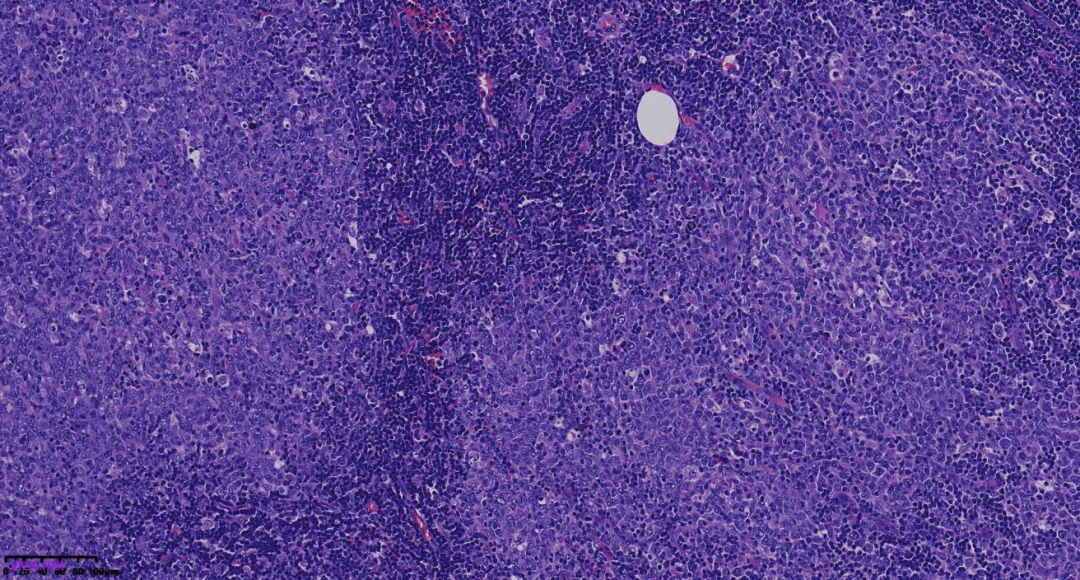

图2:结节大小不等,排列拥挤,部分结节内可见星空现象。

图3:结节似淋巴滤泡生发中心,但周围未见明显套区、边缘区存在,未见明区、暗区正常淋巴结极向,提示为肿瘤性的生发中心。

图4:结节内瘤细胞核大,呈空泡状,核仁明显,似中心母细胞,其间散在巨噬细胞,未见明确中心细胞。

图5:高倍镜显示结节内中心母细胞样细胞增生,弥漫分布,核分裂象活跃,可见星空现象,表明肿瘤增殖活性高。